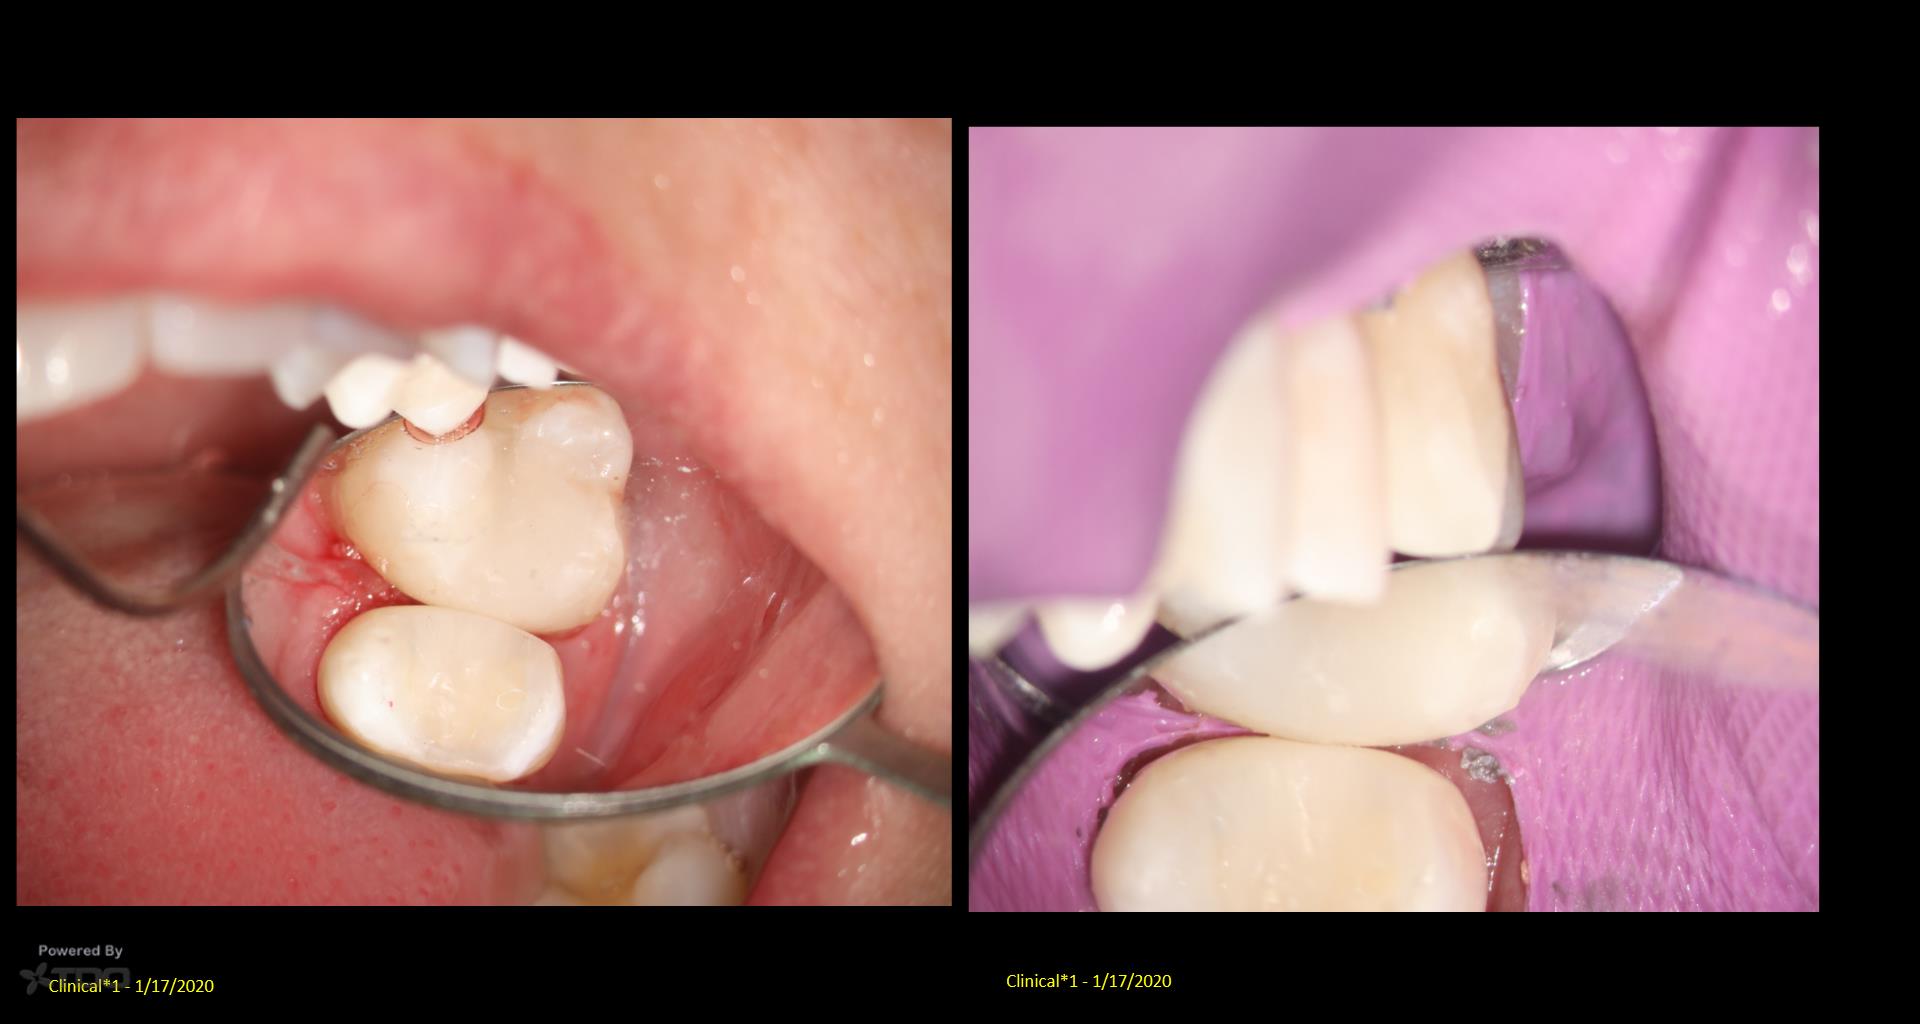

My hat is off to Dr. Ho and Dr. Dale who are doing this really well. Myself? Not too great….but I will get better….. There was caries under the DO on #13. So I tried a Clark Class 2, injected molded restoration. Took 2 hrs! I just can’t imagine doing this without a scope. Or for that matter, without an assistant’s scope. gbc